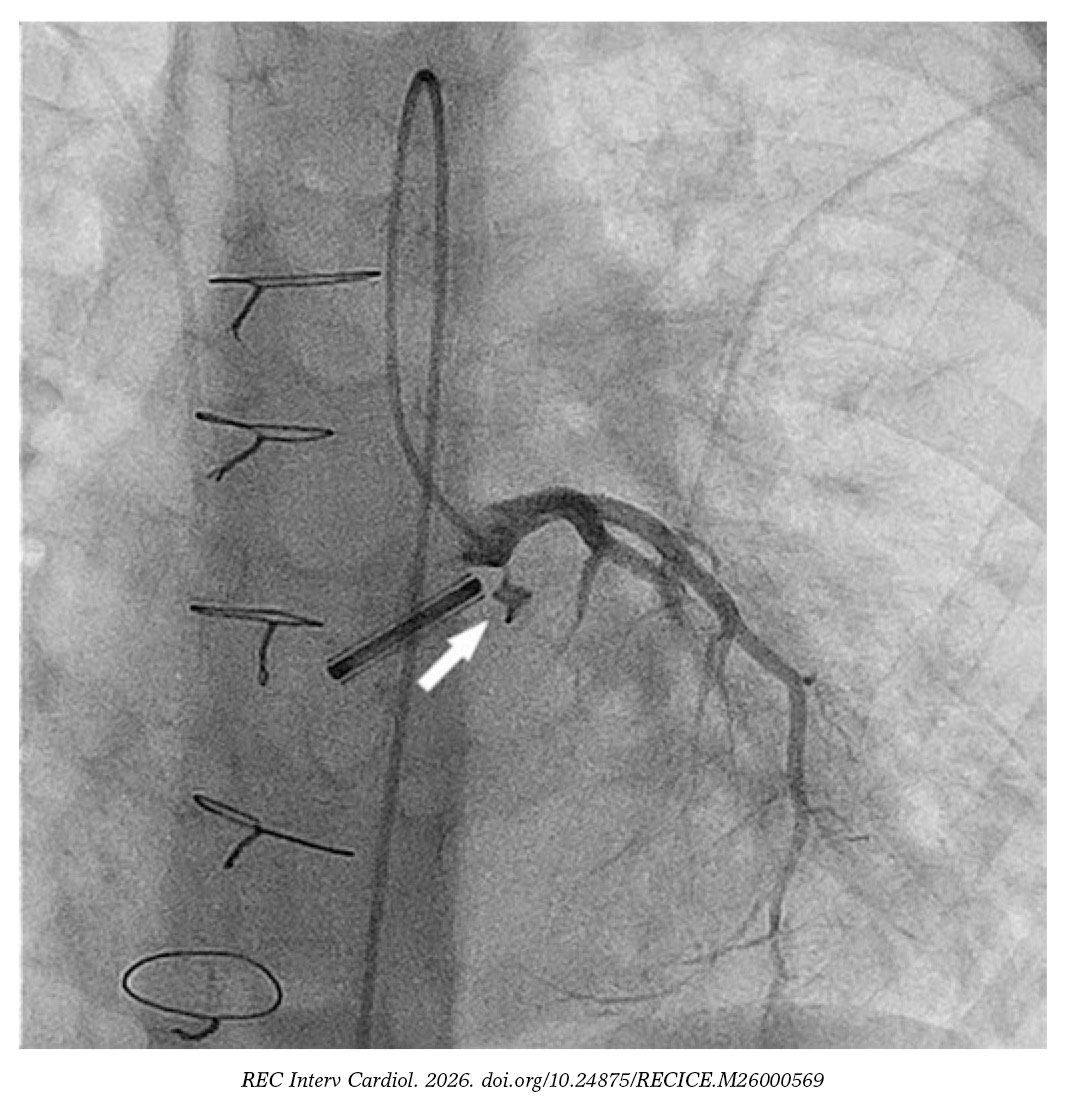

We catheterized the fistulous tract using a modified 4-Fr NIH catheter (Cordis, United States) and a 0.035 in hydrophilic guidewire. Afterwards, we mounted a 4-Fr delivery catheter over the guidewire, and deployed a 4 mm × 4-mm Nit-Occlud PDA device (PFM Medical, Germany) (figure 2 and video S2). We chose this device over nitinol mesh occluders because their greater length and retention discs were considered at risk of interfering with the coronary artery.

Figure 2.